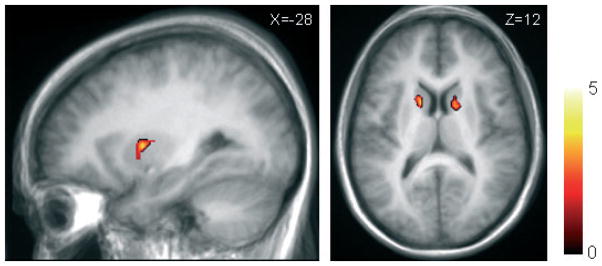

Additional analysis using SPM2 confirmed our results. Three-way ANOVA (left DLPFC, right DLPFC and vertex stimulation) showed a significant effect on BP in the left and right caudate nucleus and left putamen (F2,18 > 3.5, P < 0.005 uncorrected, extent threshold > 10 voxels). A direct contrast of the left vs. right DLPFC stimulation revealed a greater [11C]raclopride BP (i.e. reduced task-related dopamine release) in the bilateral caudate nucleus and left putamen (t9 > 2.5, P < 0.001 uncorrected, extent threshold > 10 voxels; Fig. 6).

Fig. 6.

Direct contrast of the left vs. right DLPFC stimulation showed higher BP (i.e. reduced task-related dopamine release) in the bilateral caudate nucleus (z = 12) and left putamen (x = −28; t9 > 2.5, P < 0.001 uncorrected, extent threshold > 10 voxels).